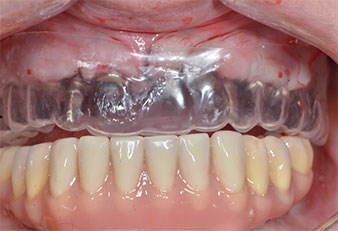

Поради сравнително твърдата кост (D2) в тази област, 10-милиметровото имплантно ложе в позиции 11 и 21 беше завършено с ротационен дрил с диаметър 4 mm в комбинация с W&H хирургичен обратен наконечник WS-75 L, W&H имплантологичен мотор Implantmed и опционалния W&H Osstell ISQ модул. За разлика от това, благодарение на меката кост, дисталните зони се подготвят до окончателен диаметър 3 mm, използвайки накрайник за Piezomed I3P. Имплантите най-накрая са поставени трансгингивално, за да остеоинтегрират за три месеца (Фиг. 6-10). Съществуващата протеза се фиксира на четирите временни импланта (Фиг. 8).

Хирургичен водач

Фиг. 9 Хирургичен водач осигурява достатъчно пространство на съществуващата протеза да служи за временна, закрепена върху временните импланти.